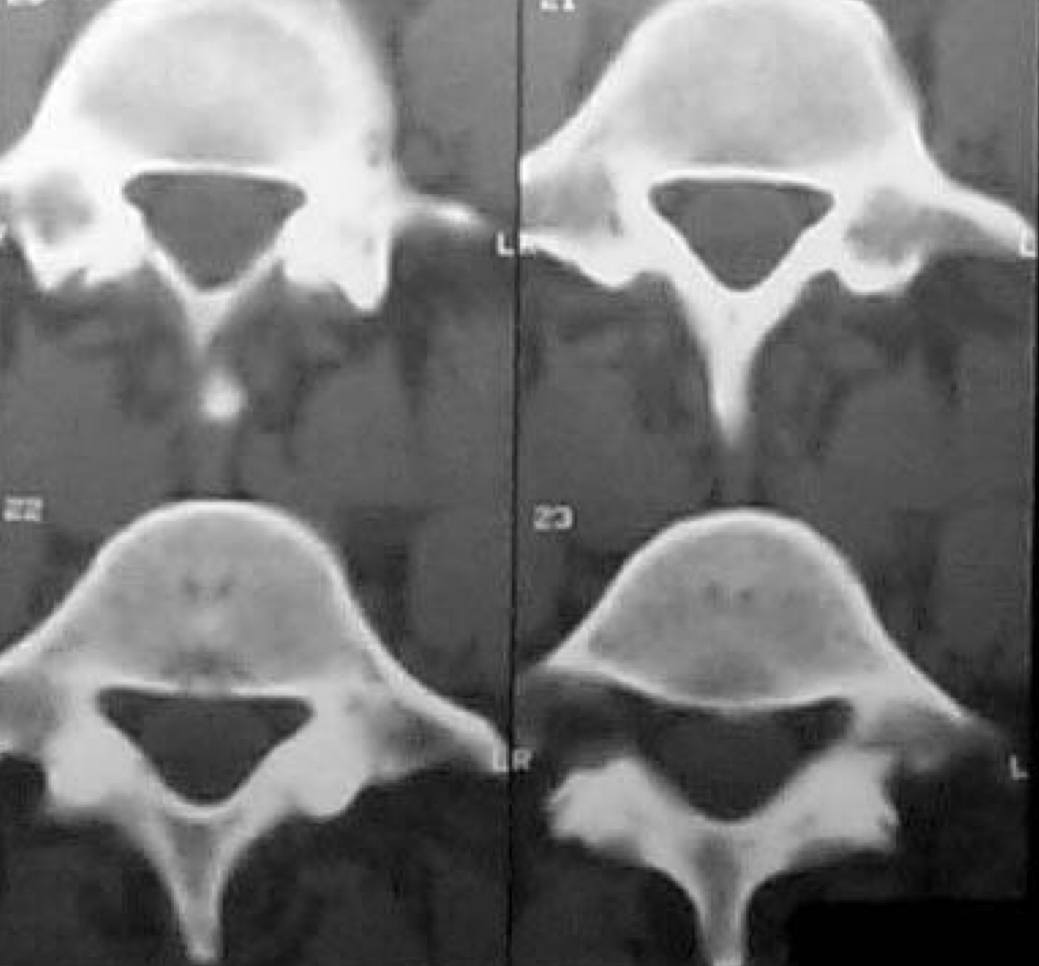

What kind of CT window is this? Why?

bone window, because the cortical bone of the vertebrae is opaque and bone features are distinguishable